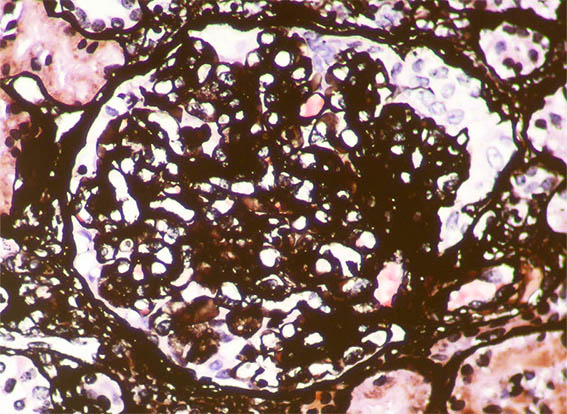

Se hace biopsia del injerto renal, observe las imágenes.

Figura 10. Plata-metenamina, X400.

Figura 11. Inmunofluorescencia para IgA, X400. Positividad mesangial y subendotelial.